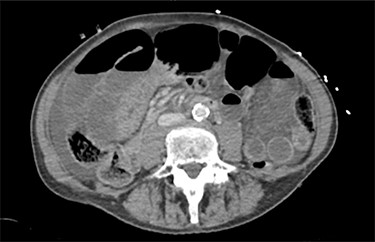

On examination she was mildly tachypnoeic, with normal oxygen saturations, heart rate was 74/min, with a blood pressure of 151/80 mmHg. On palpation, she was grossly distended, guarding and peritonitic throughout with no palpable hernias. Blood tests revealed an elevated white cell count of 13.4 × 109/l and a lactate of 2.3 mmol/l. An urgent computerized tomography (CT) scan of the abdomen and pelvis was performed. The CT demonstrated a large volume of free intraperitoneal fluid, with multiple loops of distended small bowel (Figs 1 and 2) without pneumoperitoneum. Although not noted in the report, there was concern about a ‘swirl’ in the mesentery, raising the possibility of a small bowel volvulus (SBV).

The patients CT scan, axial slice showing distended loops of small bowel and free fluid.